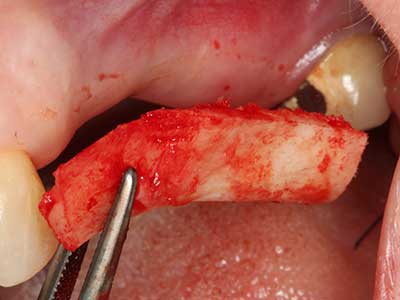

Indicazione: prelievo osseo autologo

I trapianti autologhi dell'osso si eseguono in forma di blocchi, strati e anelli, anche in combinazione con materiali di riempimento tipo microframmenti. Se il sito dell'impianto viene preparato contemporaneamente all'accrescimento, diversi sistemi di filtraggio dell'osso si sono rivelati efficaci per la raccolta dei microframmenti ossei risultanti. Come metodo alternativo, il sito dell'impianto può essere preparato utilizzando un dispositivo a bassa velocità senza irrigazione. Senza l'inserimento di un impianto, è possibile raccogliere i microframmenti ossei dalla periferia mediante bisturi affilati per tessuto osseo. Ciò può essere eseguito anche con la piezochirurgia mediante appositi raccordi che raccolgono microframmenti ossei di qualità più elevata rispetto a quelli raccolti con trapani rotondi, come è stato confermato in uno studio comparativo dei due metodi (Chiriac, Herten et al. 2005).

La piezochirurgia presenta altri vantaggi per quanto riguarda la raccolta di blocchi ossei. Oltre all'elevata precisione dell'osteotomia appena descritta, l'utilizzo di puntine per sega molto sottili permette di minimizzare in maniera significativa la perdita di materiale. È molto probabile che si verifichi una maggiore perdita di materiale durante la raccolta utilizzando puntine di strumenti più spessi, in particolare delle frese Lindemann (Lakshmiganthan, Gokulanathan et al. 2012). La separazione basale, necessaria in particolare per i trapianti di blocchi nella zona retromolare, viene semplificata grazie a seghe specificatamente progettate di forma rettangolare; di conseguenza la piezochirurgia è considerata una procedura precisa, semplice e sicura per la raccolta di blocchi di osso nella zona retromolare (Happe 2007) (figg. 1-12).